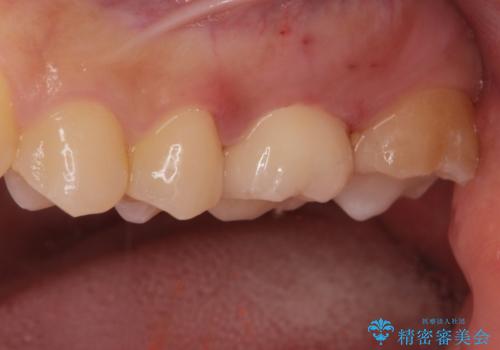

適合の良いクラウン、詰め物が入りました。

適合が良いことで虫歯の再発のリスクが低くなります。

- ジルコニアクラウンスタンダード・仮歯 12.1万円 e-maxインレー 7.7万円費用は治療当時の料金となります